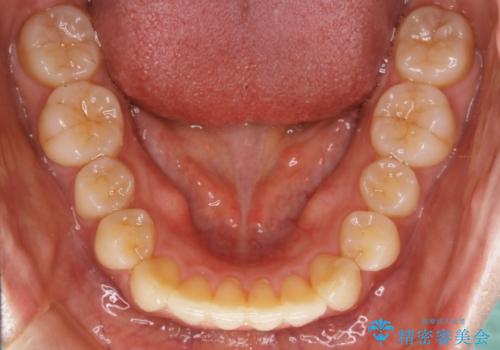

- 上下の歯のガタつきを主訴にご来院されました。

前歯部に特にガタつきが見られ、正中もズレている状態でした。

矯正装置の希望がインビザラインだったため、マイクロインプラントを併用し、奥歯から順に遠心移動をかけていくことにより非抜歯でも主訴のガタつきを治すことができました。

マウスピースとマイクロインプラントを組み合わせることで、抜歯をしなくても歯並びを治すためのスペースを作ることができます。奥歯から順に移動させていくので前歯に変化が出るまでには時間がかかりますが、その分健康な歯を抜歯することなく理想的な歯並びを手に入れることができます。